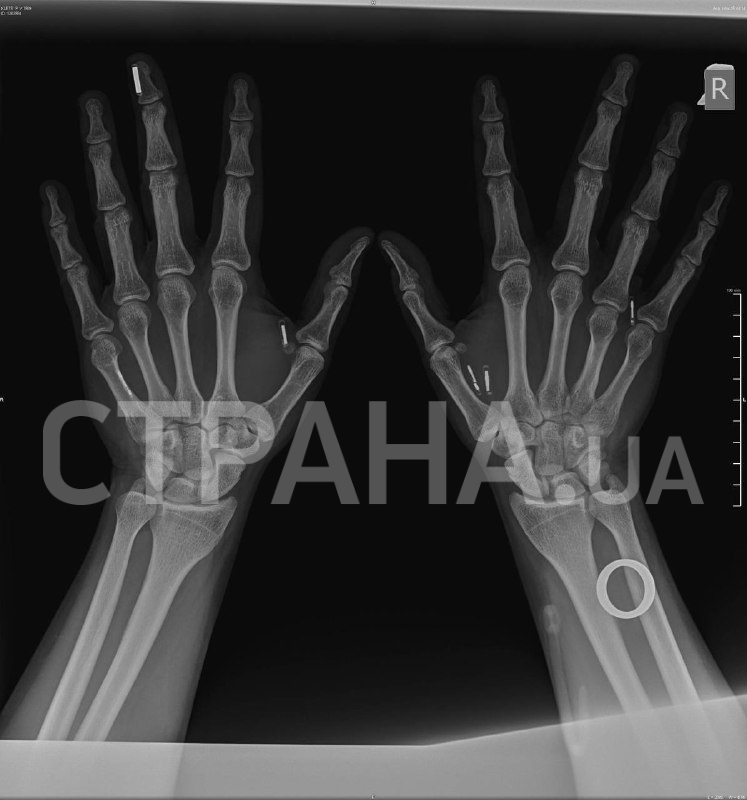

Восемь миниатюрных чипов в руках Клеца позволяют расплачиваться за покупки, заводить авто и многое другое, не пользуясь дополнительными гаджетами.

– Когда я ехал на пресс-брифинг, где мне вживили восьмой чип, очень переживал, что столкнусь со шквалом критики, что меня будут поджидать какие-то фанатики, чтобы напасть на меня или еще что-то. Но реакция была совсем иной, я, честно, даже не ожидал, что все к этому отнесутся с пониманием и интересом. Дело в том, что имплантаты, электронные или нет, давно существуют в нашей жизни: люди ставят себе зубы, ремонтируют кости. Вы же не отказываетесь от гипса, потому что он надевается на руку. Люди не отказываются от спиц в руке, хотя это то же самое, что вживить чип. Я не до конца понимаю, в чем разница между имплантируемой электроникой и любым другим имплантом, но все равно уважаю мнение этих людей, пусть оно будет.

– Иными словами, у вас в руке сейчас находится платежное кольцо, которое предназначено для внешнего ношения на пальце и оплаты им по платежному терминалу?

– Совершенно верно. Его нужно было правильно стерилизовать для интеграции под кожу. Находясь в стерильном пакете и пройдя все процедуры, оно продолжило быть рабочим устройством. То есть устройство, которое было сделано для ношения на пальце. Нам оставалось только взять и попробовать. Мы взяли и попробовали, я два месяца им пользуюсь, все работает, все круто.